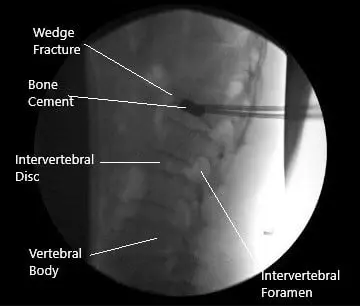

Intraoperative fluoroscopic image of kyphoplasty.

Bone cement was mixed and inserted on right and left sides. About 4 ccs of cement could be inserted. There was a suspected breach of the inferior endplate, but the cement was still in the vertebral body. The tamps were put into the sleeves till cement was hardened. The sleeves were removed. The final picture was taken in the AP and lateral view and saved. The wound was thoroughly washed.